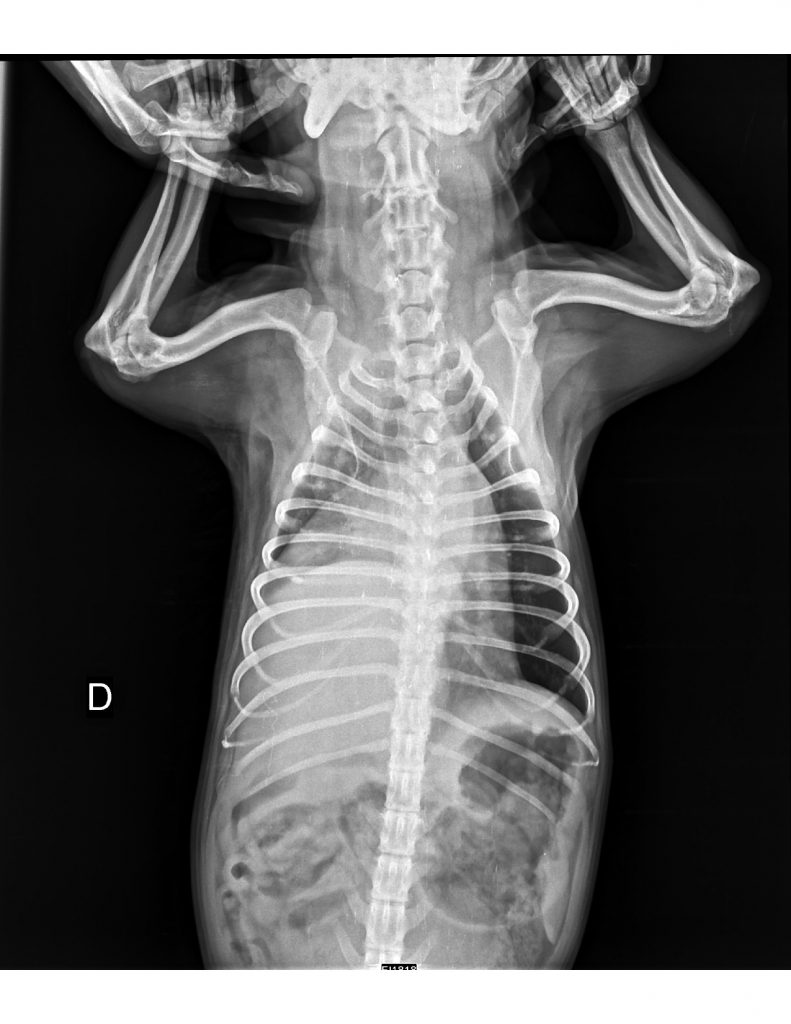

Ingresa a consulta un paciente macho canino con distress respiratorio. Los tutores indican que respira de ese modo hace semanas y que presentó pneumonia diagnosticada en otro centro veterinario hace 6 meses.

Se obtiene radiografía L-L y V-D de tórax:

Foto 1.